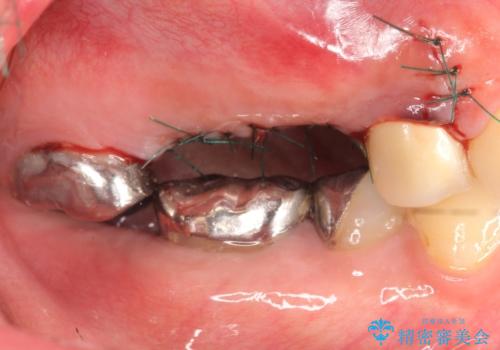

右上の567ブリッジを外したところ、右上5は歯根破折により保存不可能だったため、右上56部にインプラントを埋入し欠損補綴を行いました。

また右上5部に関しては抜歯時に歯槽堤保存術(抜歯窩に人工骨の填入を行う手術)を行い、骨の欠損を最小限に止めています。